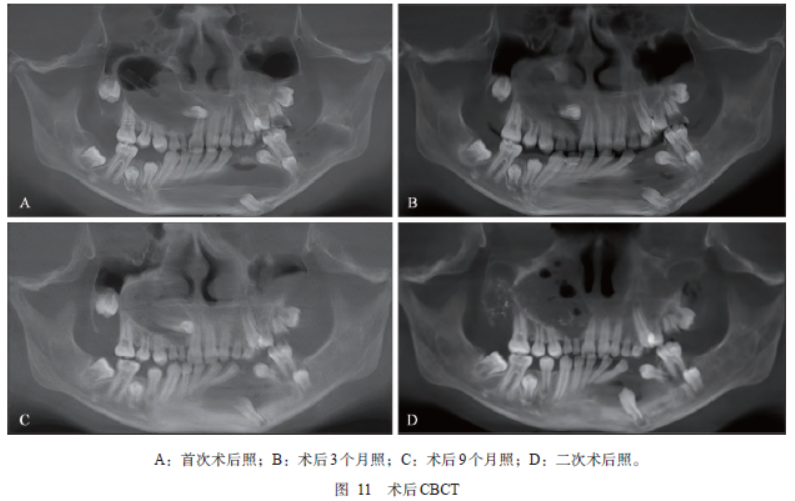

治疗经过:1)口腔外科手术治疗——小囊肿手术单纯刮治术,大囊肿一期开窗减压术,二期刮治术,术中照见图9;术后病理(图10)确诊多发性牙源性角化囊肿(odontogenic keratocyst,OKC);2)术后1年复诊时发现上颌引流不畅,管道堵塞,管上段大量角化物,收治入院拟行二次手术,行颌骨囊肿刮治术,术后CBCT示与首次术前CBCT相比,左下后牙区及右下后牙区颌骨囊腔基本消失,下颌颏部囊腔新骨进一步形成,囊腔较前缩小,上颌骨囊腔边缘新骨形成效果较差,各时期CBCT影像见图11。

最常见于下颌骨,上颌骨OKC发生率虽较下颌骨低,但它们比下颌骨OKC更具有复发性和难治性。在本病例中,术后复查结果也反映了相似的问题,相同的手术方式,上颌囊肿术后囊腔边缘成骨效果差于下颌骨,上颌骨OKC更具难治性。OKC是这种疾病的常见标志之一,即使在没有并发其他临床表现的情况下,也应该引起接诊医生的高度怀疑,皮肤多发性BCC也是NBCCS最具特征性的表现之一。